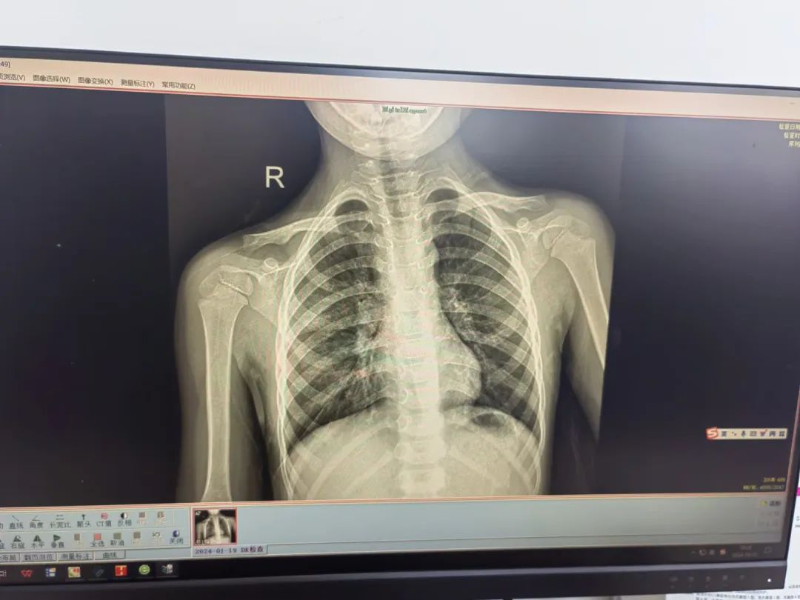

門診胸片結果顯示,帆帆的右上肺存在感染并伴有實變,結合其臨床表現,門診醫生判斷帆帆患上了兒童社區獲得性肺炎,即刻安排他入住普兒科接受治療。住院期間,普兒科副主任醫師陳玲與龍斌每天輪流多次巡房查看帆帆的病情,并耐心細致地診治。陳玲為他制定了個性化的治療方案,時刻關注其病情變化,確保治療方案的有效性和安全性。

治療前(左)、后(右)胸片對比

經過9天的精心治療,帆帆的咳嗽和高熱癥狀已完全消失。在出院前,護士們和家屬詳細講解了出院后的注意事項和防護措施,確保帆帆能夠在出院后繼續得到良好的護理和康復。家屬對醫生的治療效果和貼心服務表示衷心的感謝,并手寫一份感謝信贈與醫護人員。